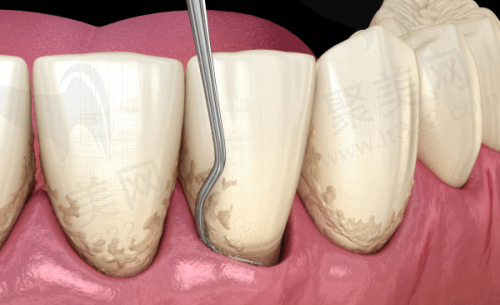

技术特点:开展了微创种植、ALL - ON - 4半口/全口修复等技术。微创种植能减少手术创伤,让患者术后修复更快;ALL - ON - 4半口/全口修复技术则可以用较少的种植体实现半口或全口牙齿的修复,大大缩短了治疗时间。

牙齿矫正项目

矫正方案:医院提供传统金属矫正器、陶瓷矫正器和隐形矫正(如隐适美)等多种方案。方案设计比较灵活,无论是青少年还是成年人,都能找到适合自己的矫正方式。